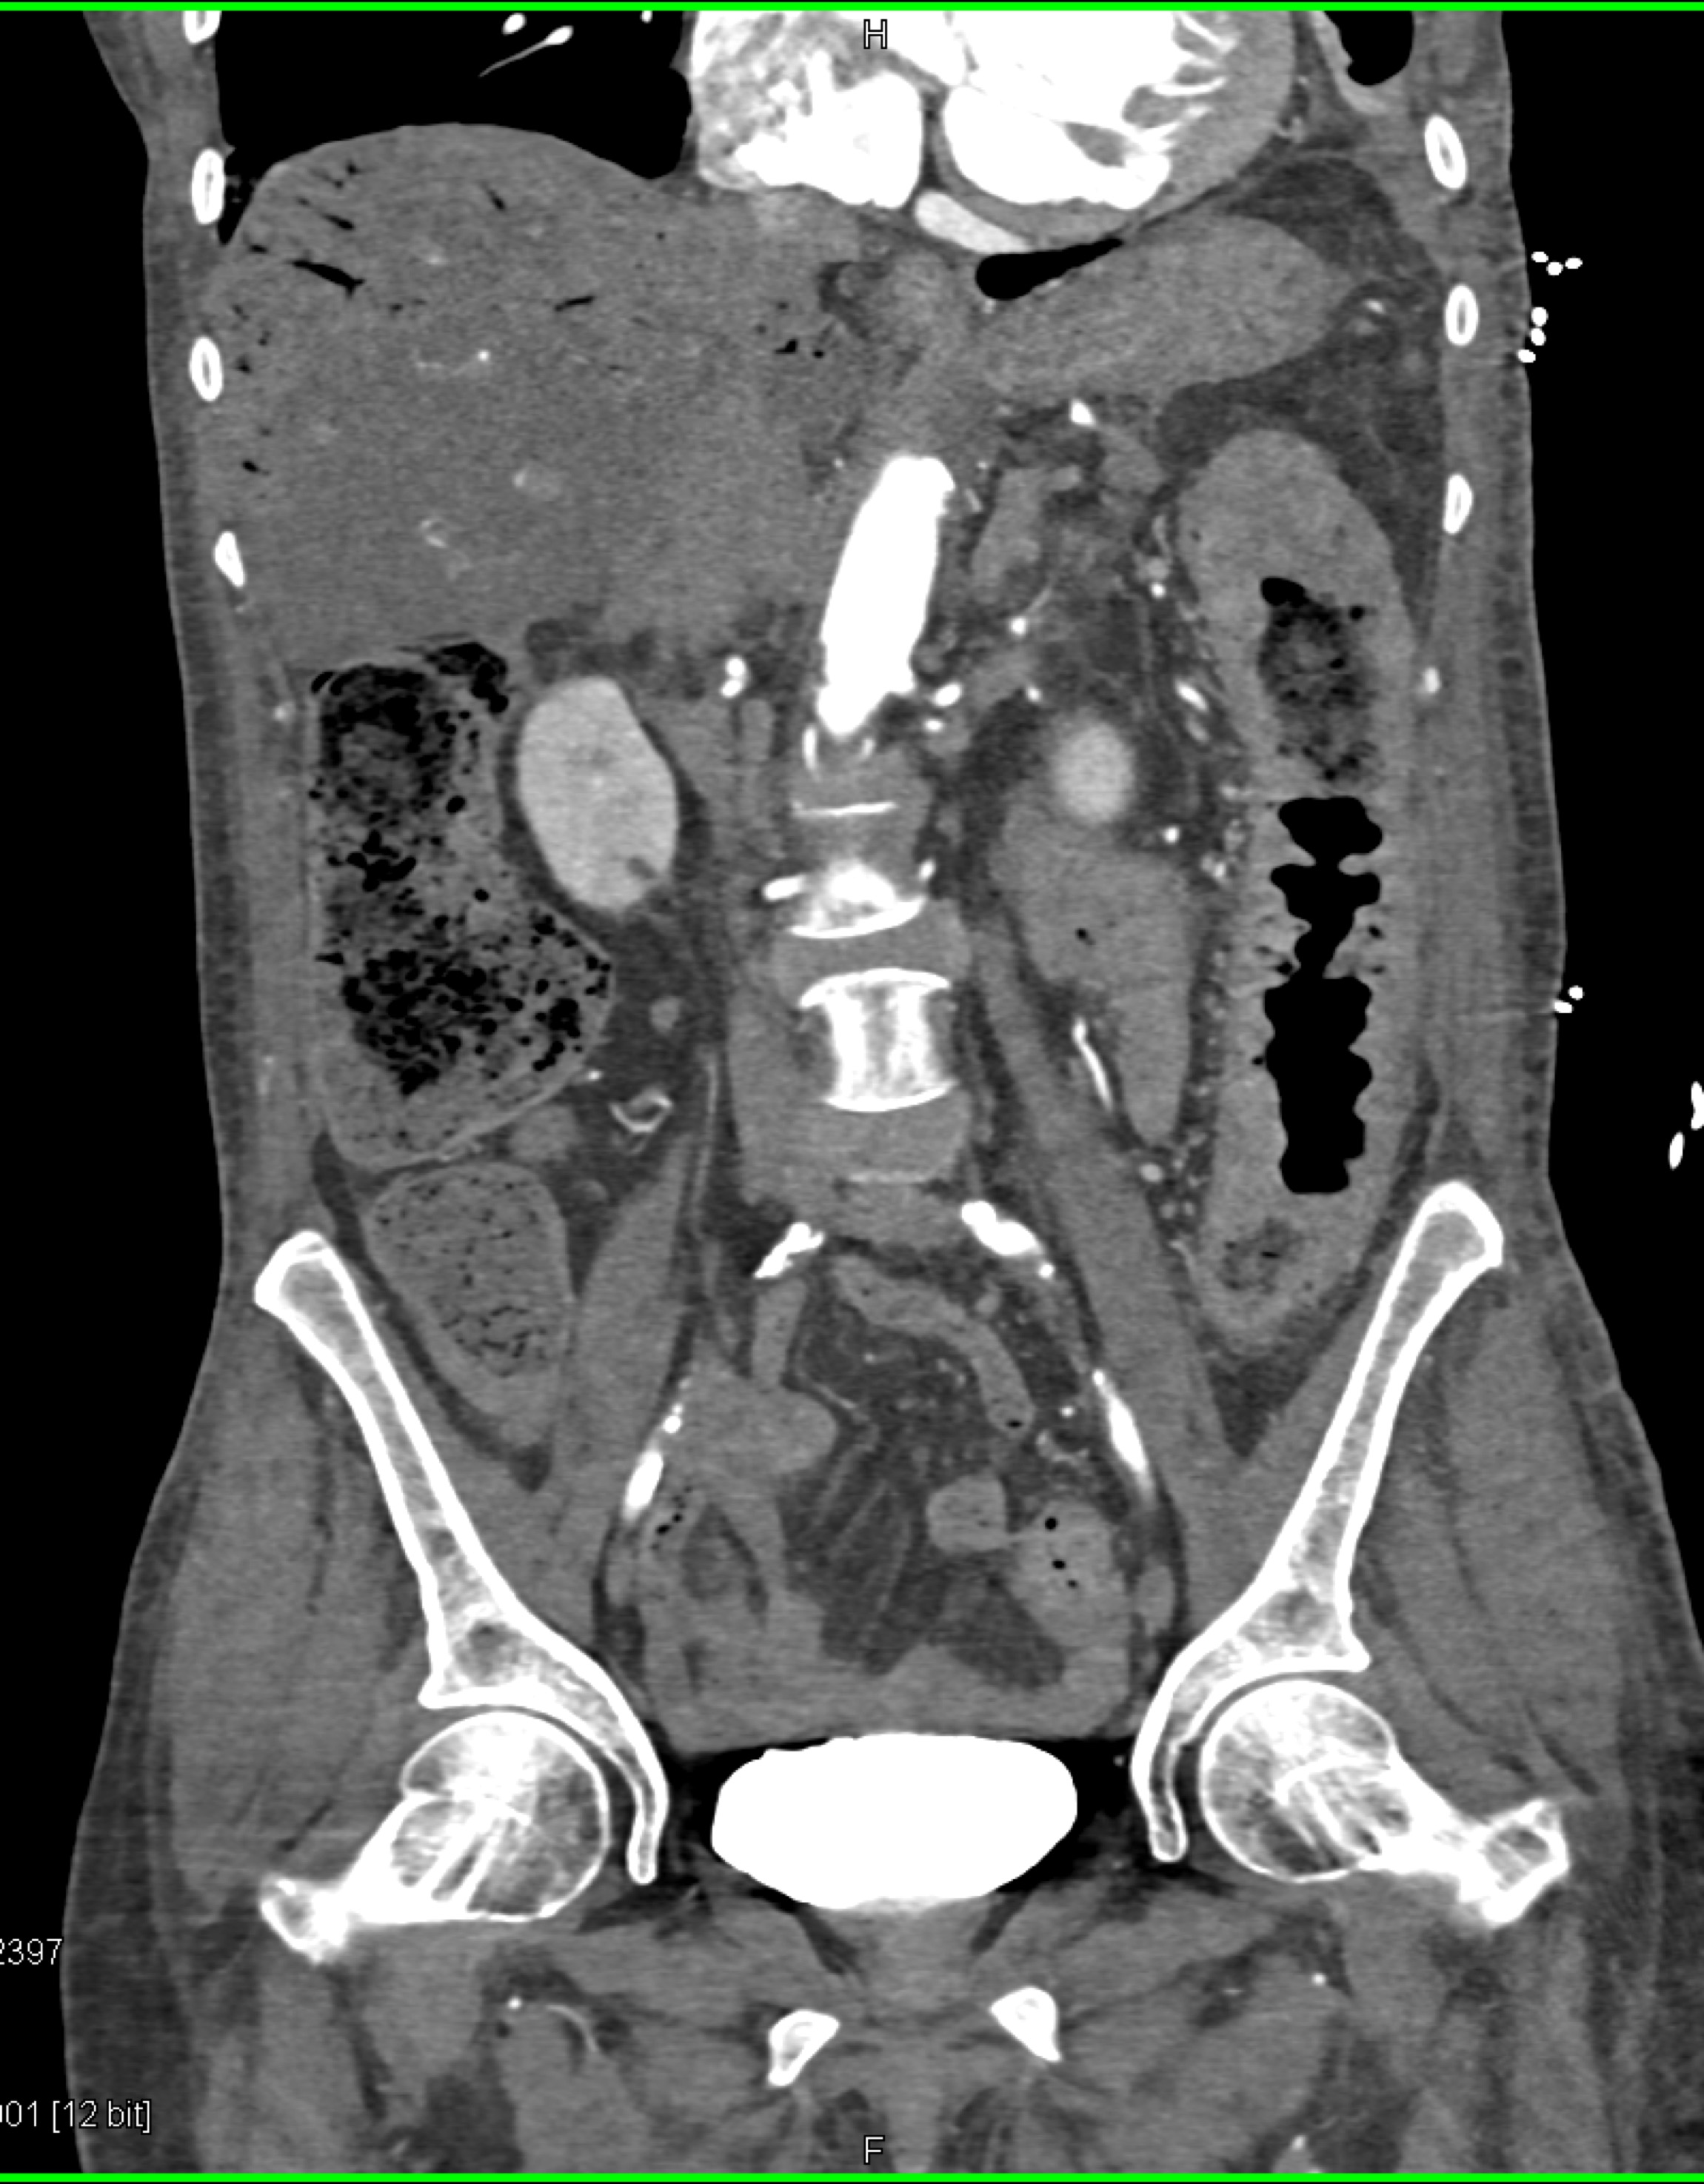

7) In this patient with GI bleed and fever the most likely diagnosis is?

liver abscess

liver abscess and diverticulitis

liver tumor and bowel cancer

liver abscess and chicken bone in appendix